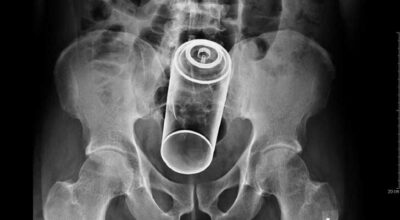

Esta recopilación de imágenes recoge alguna de las situaciones más estrambóticas que se han podido dar en una sala de rayos X. Todas ellas tienen algo en común: Son objetos extraños para el cuerpo humano que, de alguna manera han encontrado una vía de entrada, pero se han perdido a la hora de encontrar la de salida.

Muñecas de juguete descabezadas, botellas, armas, frascos, botes de plástico, teléfonos y hasta una cinta de casete pueden encontrarse en esa suerte de “punto limpio” al que ha quedado reducido el interior de los afectados.

No sabemos, ni juzgamos, la forma o los motivos por los que terminaron atrapados en dichas partes del cuerpo, pero estamos convencidos de que algún doctor estuvo al borde de la carcajada cuando se encontró con casos tan llamativos e inverosímiles como estos ¡Ver para creer!